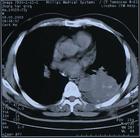

放射性肺損傷

急性放射性肺炎是危害性較大的併發症。照射劑量3000—4000cGy3—4周后,所照射的肺呈現急性滲出性炎症。每一位肺部照射的病人都有這種改變,但大多數不產生症狀,此時若有感染即產生症狀,叫急性放射性肺炎。若不產生症狀,照射結束後,炎症逐步吸收、消散,逐漸形成不同程度的肺實質的纖維變。肺纖維化發生於照射後6個月左右,逐漸加重,到一年達到最嚴重的地步。

放射性肺炎的形成與照射面積關係最大,與劑量及分割、機體因素、個體差異、有無慢性肺疾病與放射性肺炎的發生也有一定的關係。放療中並用ADM、PYM、VCR等抗癌藥及吸菸也易促使放射性肺炎的發生。放射性肺炎的治療主要是用大劑量的抗生素及腎上腺皮質激素,尤其是大劑量使用腎上腺皮質激素連續數周。其他可給予支氣管擴張劑等對症治療。